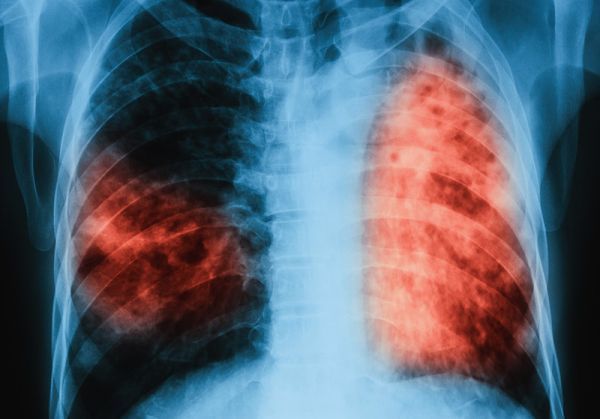

Кампанията се провежда съвместно с Министерство на здравеопазването и Столична община, със съдействието на Института за здравно образование. Прегледите се извършват в мобилен кабинет – флуорограф, включени са флуорография на бял дроб и спирометрия – измерване количеството на издишания въздух.

През 2018 г. са изследвани 437 души. При 138 от тях се установи Хронична обструктивна белодробна болест (ХОББ), която е била недиагностицирана до момента.

Хроничната обструктивна белодробна болест (болестта на пушачите) е вече на трето място в света като причина за смърт. От 10-те най-смъртоносни болести 4 са белодробни: ХОББ, остри инфекции на долните дихателни пътища, карцином на белия дроб и туберкулоза.